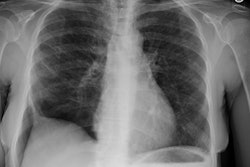

OBJECTIVE. We reviewed the imaging findings in nine patients with idiopathic giant bullous emphysema. This progressive condition is characterized by large bullae, usually seen in association with several forms of emphysema, and usually occurs in young men, most of whom are smokers. MATERIALS AND METHODS. Nine patients with chest radiographic evidence of a bulla or bullae occupying at least one third of a hemithorax, who had also been examined with high-resolution CT, were included in this retrospective study. We examined the size, distribution, and locations of bullae. On high-resolution CT scans, bullae were categorized as predominantly subpleural or intraparenchymal. RESULTS. In eight of the nine cases, the chest radiographs showed variable asymmetry in the distribution of bullae. Bullous disease involved predominantly the upper lobes. High-resolution CT showed bullae from 1 to 20 cm in diameter, but most were 2-8 cm in diameter. Paraseptal emphysema and subpleural bullae were the predominant findings in all nine patients. Seven patients had separate centrilobular emphysema of various degrees and intraparenchymal bullae. None of the intraparenchymal bullae were larger than 2-3 cm. Additionally, two non-small-cell lung cancers were seen in our series. CONCLUSION. The dominant and consistent feature seen on high-resolution CT scans in both smokers and nonsmokers is extensive paraseptal emphysema merging into giant bullae. Associated centrilobular emphysema, seen in cigarette smokers, is the important variable finding for determining the extent of underlying parenchymal disease, which may help in the preoperative assessment of giant bullous lung disease.